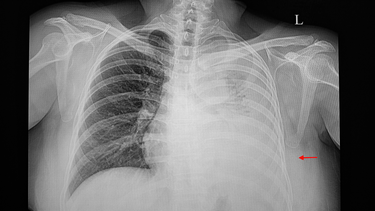

Ung thư phổi giai đoạn cuối, đặc biệt là khi đã di căn đến các cơ quan quan trọng như não, từ lâu được xem là “bản án tử” đối với người bệnh. Tuy nhiên, với sự tiến bộ vượt bậc của y học hiện đại, nhiều trường hợp ung thư phổi giai đoạn cuối vẫn có thể được kiểm soát tốt và kéo dài thời gian sống đáng kể, thậm chí lên đến nhiều năm.

Trên thực tế, ngày càng có nhiều bệnh nhân ung thư phổi giai đoạn 4, bao gồm cả những trường hợp đã di căn lên não, có thể sống khỏe mạnh hơn 5 năm và vẫn đang duy trì các chỉ số sức khỏe ổn định. Một số người bệnh còn có thể sống thêm 7 – 8 năm, thậm chí lên tới 10 năm nếu đáp ứng tốt với phương pháp điều trị phù hợp.

Kéo dài tuổi thọ cho bệnh nhân ung thư phổi không phải là điều bất khả thi, nếu người bệnh được phát hiện sớm, điều trị đúng hướng và nhận được sự chăm sóc toàn diện cả về thể chất lẫn tinh thần. Trong những năm gần đây, nhờ sự tiến bộ của y học, nhiều phương pháp điều trị ung thư phổi đã mang lại kết quả khả quan hơn. Chẳng hạn, hóa trị, xạ trị, phẫu thuật, liệu pháp nhắm trúng đích (targeted therapy) và miễn dịch (immunotherapy) đang được áp dụng linh hoạt, tùy theo giai đoạn và đặc điểm sinh học của khối u. Đặc biệt, nếu ung thư được phát hiện ở giai đoạn sớm, khả năng kéo dài tuổi thọ, thậm chí kiểm soát lâu dài, là điều hoàn toàn có thể.